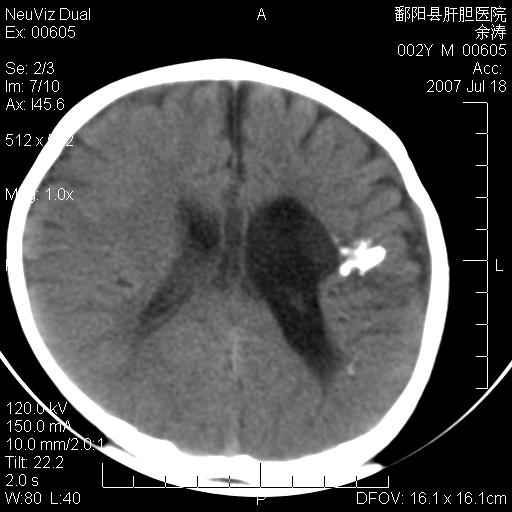

男性 2岁:平时智力障碍。外伤后行颅脑平扫。

左颞叶“萎缩”,可见不规则高密度影,并左侧室扩大,呈负占位效应...支持考虑先天发育异常(血管发育畸形)可能性大,建议结合进一步检查了解。

左颞叶“萎缩”其内可见不规则点条状高密度影,并左侧室扩大,考虑颅面血管瘤病

脑裂畸形;左侧脑脑萎缩;透明隔囊肿;血管畸形?

开唇型脑裂畸形

左侧颞顶叶钙化灶,其内有小片状低密度影 边缘清晰。与之相邻的脑沟增宽增深 ,左侧侧脑室体部牵拉扩大。考虑左颞顶软化灶并局限性脑萎缩。透明隔间腔。

该病人应该还有胼胝体发育不全